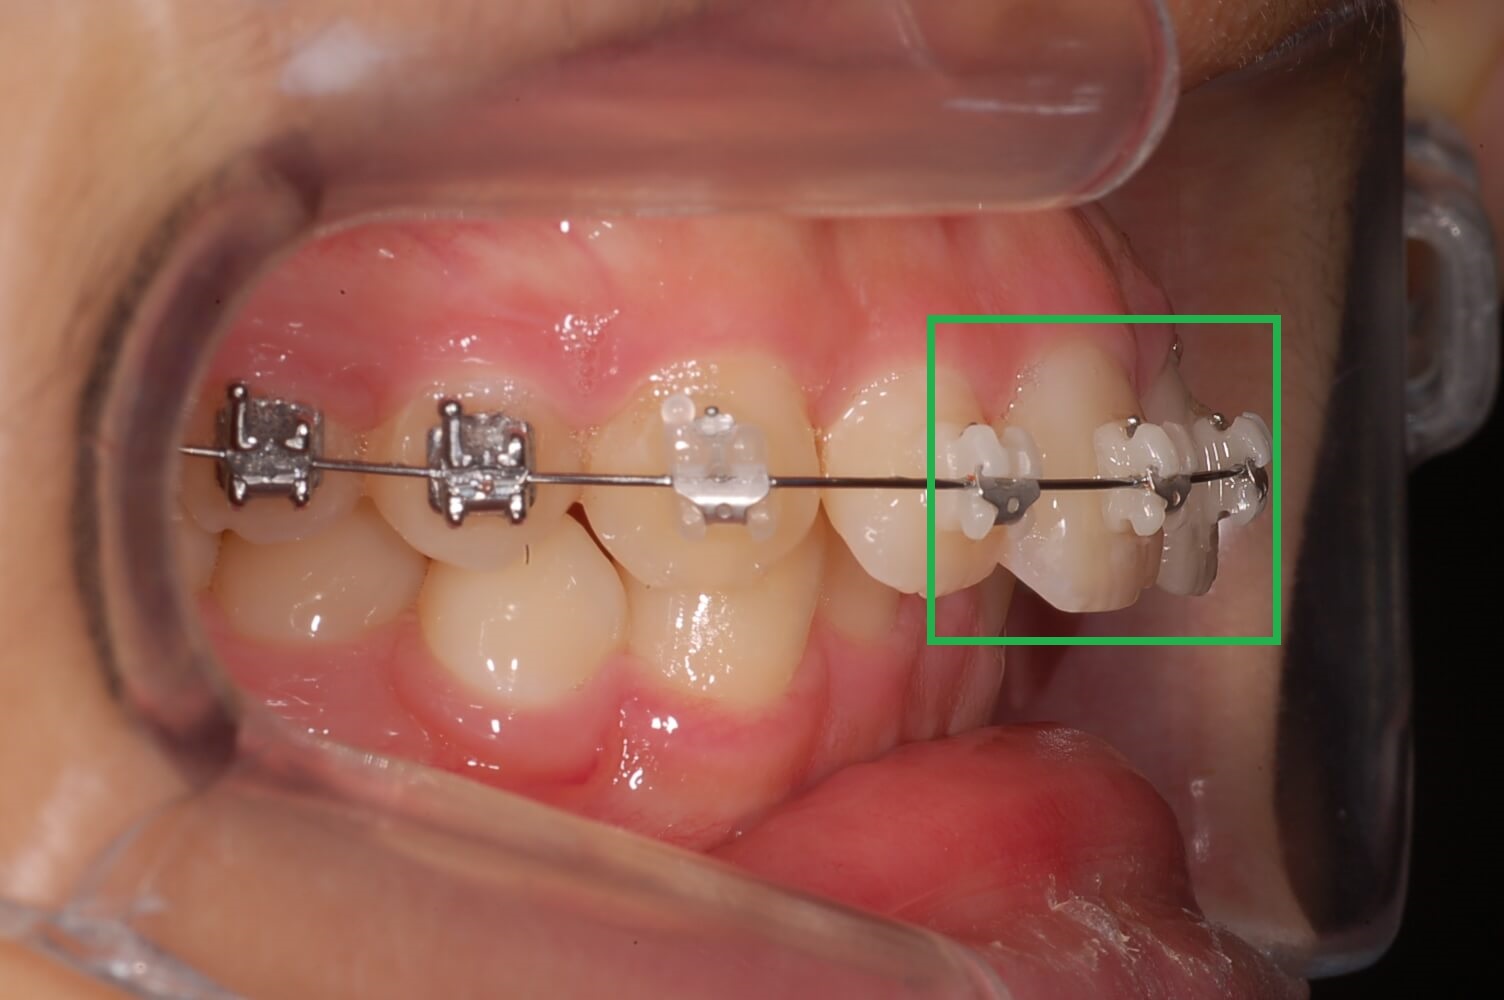

2. 가위교합 교정실시 (3개월 상태)

사진을 보시면 거의 정상으로 돌아왔습니다. 사실 이때 이 정도면 그냥 살아도 되지 않나 하는 생각도 해보았습니다.

하지만 이 상태로 두면 치아는 복원력이 강해 다시 누울 수 있고 어금니가 일어섬으로써 다른 치아들과 맞물리는 높이가 맞지 않아 더 큰 문제 발생된다는 것을 알았습니다.

윗 어금니는 생각보다 제자리에 돌아오는 속도가 늦었으나 전체 블라켓을 설치하고 과개교합 교정에 들어갔습니다.

▼ 3개월 후 어금니 가위교합 교정상태(아래 어금니)

▼ 3개월후 어금니 가위교합 교정상태(윗 어금니)